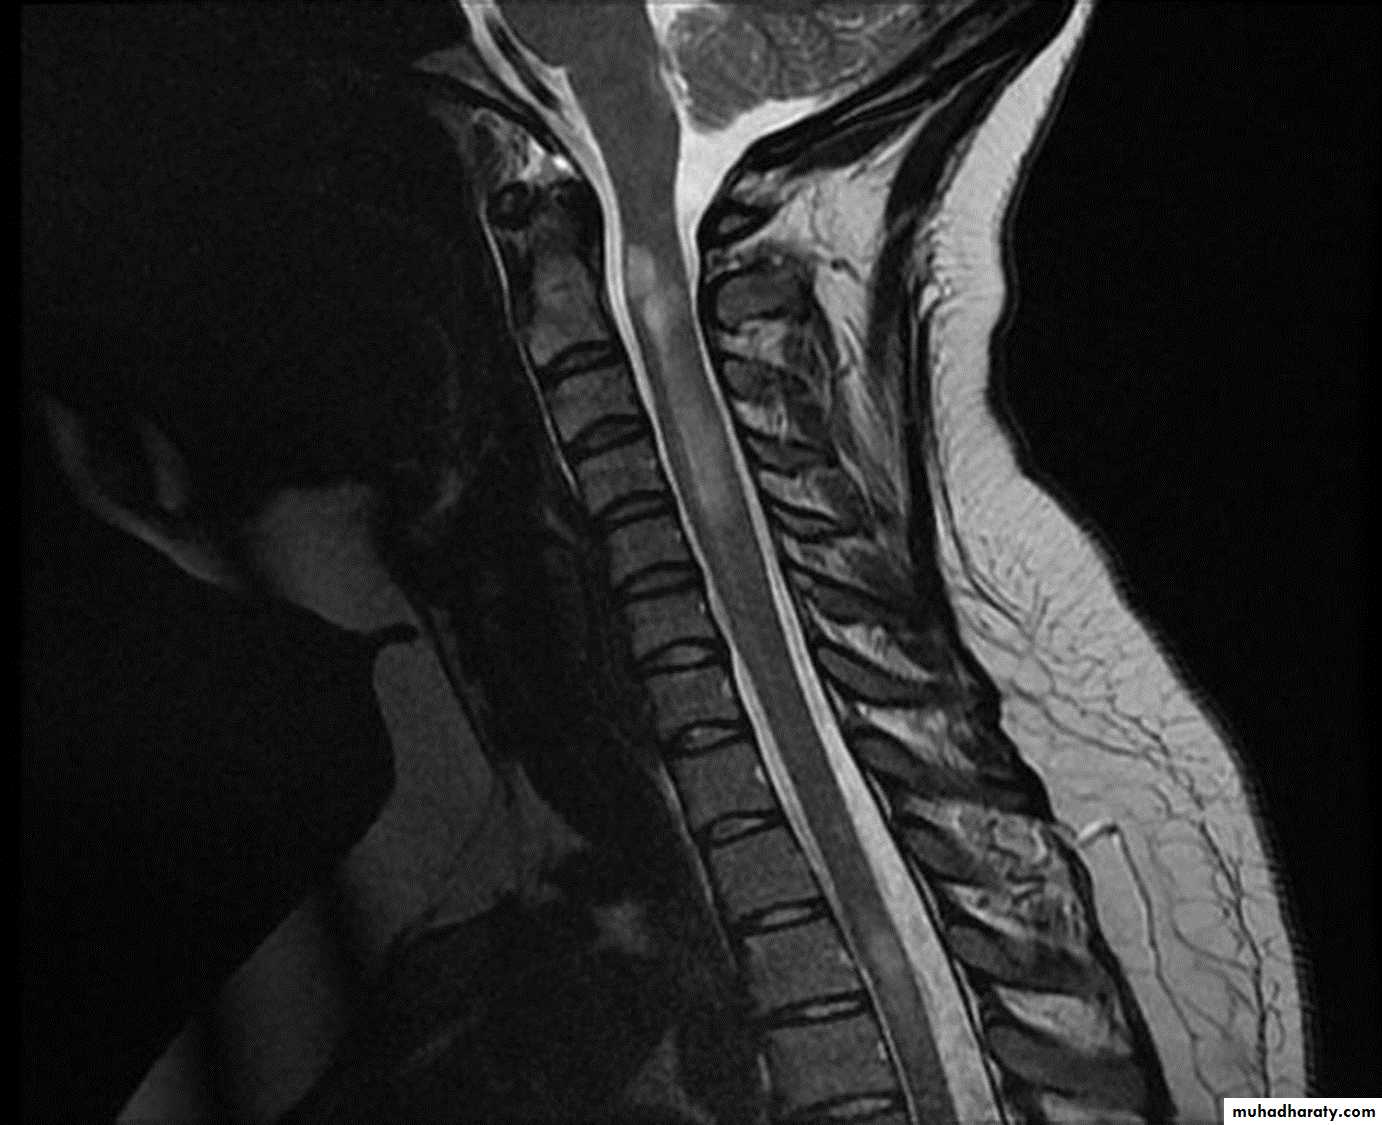

MRI :characteristic abnormalities are found in >95% of patients, although more than 90% of the lesions visualized by MRI are asymptomatic

Lesions are frequently oriented perpendicular to the ventricular surface,(Dawson’s fingers)

Lesions larger than 6 mm located in the corpus callosum, periventricular white matter, brainstem, cerebellum, or spinal cord are particularly helpful diagnostically

myelitis can be severe and transverse (rare in MS) and is typically longitudinally extensive, involving three or more contiguous vertebral segments

A T2-weighted MRI image of her spinal cord shows a lesion extending from T1 to T5 and affecting the central cord. The lesion shows patchy enhancement with gadolinium.

Neuroimaging characteristics are critical for diagnosis. Identification of an intramedullary cord lesion, especially postgadolinium enhancement, is very helpful in a diagnosis of myelitis

1. MRI of spinal cord with and without contrast (exclude compressive causes).